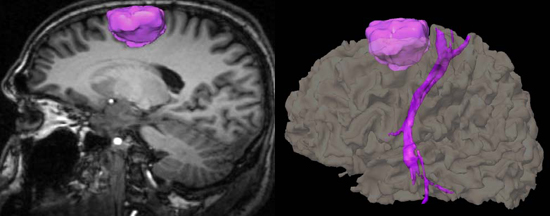

La exploración de RM en neurorradiología puede utilizar algunas técnicas especiales como son la espectroscopia, difusión, perfusión, angiografía, la tractografía y RM funcional que permiten obtener información metabólica, de movimiento molecular microscópico, de la hemodinámica cerebral, de las arterias y venas, de la estructura de las fibras cerebrales y de la actividad cerebral. Estas técnicas se emplean para el estudio de enfermedades vasculares, tumores, procesos neurodegenerativos y de forma previa a la cirugía cerebral para evitar lesionar zonas importantes del cerebro.

Tractografía por Resonancia Magnética.

Se muestra en color un tumor cerebral y su relación con las fibras motoras.